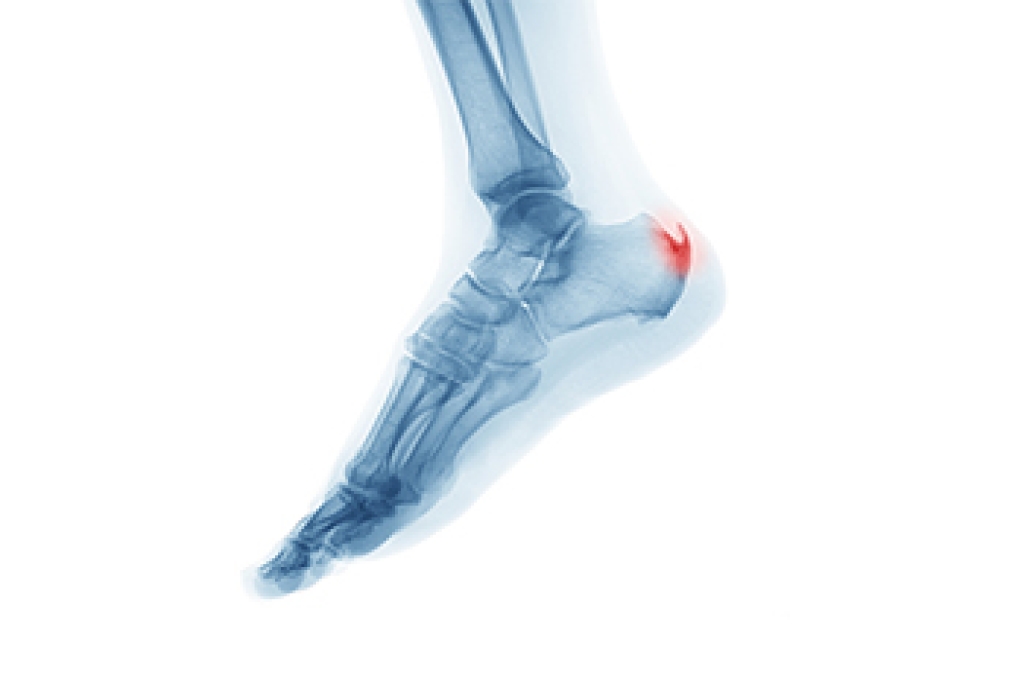

Understanding the Plantar Calcaneal Spur

A plantar calcaneal spur, often referred to as a heel spur, is a small bony projection that forms on the underside of the heel bone. It often develops over time as the body responds to repeated strain where the plantar fascia attaches to the heel. This added bone growth may or may not cause pain, but when symptoms are present, they are commonly felt with the first steps after rest or during prolonged standing. The discomfort is often linked more to irritation of the surrounding soft tissue than the spur itself. Evaluation focuses on identifying the source of strain and how the foot functions during movement. Treatment may include wearing supportive footwear, cushioning, stretching, and custom orthotics to reduce pressure on the heel. Addressing contributing factors early can help limit ongoing irritation and improve comfort. If heel pain is affecting your daily routine, it is suggested that you see a podiatrist for a proper diagnosis and appropriate treatment.

Heel spurs are formed by calcium deposits on the back of the foot where the heel is. This can also be caused by small fragments of bone breaking off one section of the foot, attaching onto the back of the foot. Heel spurs can also be bone growth on the back of the foot and may grow in the direction of the arch of the foot.

Older individuals usually suffer from heel spurs and pain sometimes intensifies with age. One of the main condition's spurs are related to is plantar fasciitis.